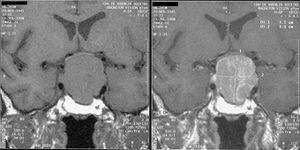

وإذا بدأ العلاج خلال فترة الطفولة يُمكن السَّيطرة على العملاقيَّة بزيادة نشاط الغدة النُّخاميَّة عن طريق العلاج بالإشْعاع. وفي بعض الحالات تزال أورام الغدَّة عن طريق الجراحة. وبإِمكان الجرَّاح أن يصل إلى الورم من خلال التجويف الأنفي، قاطعًا خلال قاع الجمجمة ليصل إِلى الغدَّة النُّخاميَّة. ولاتبدو على المريض أي آثار ندبات بعد إِجراء العملية.